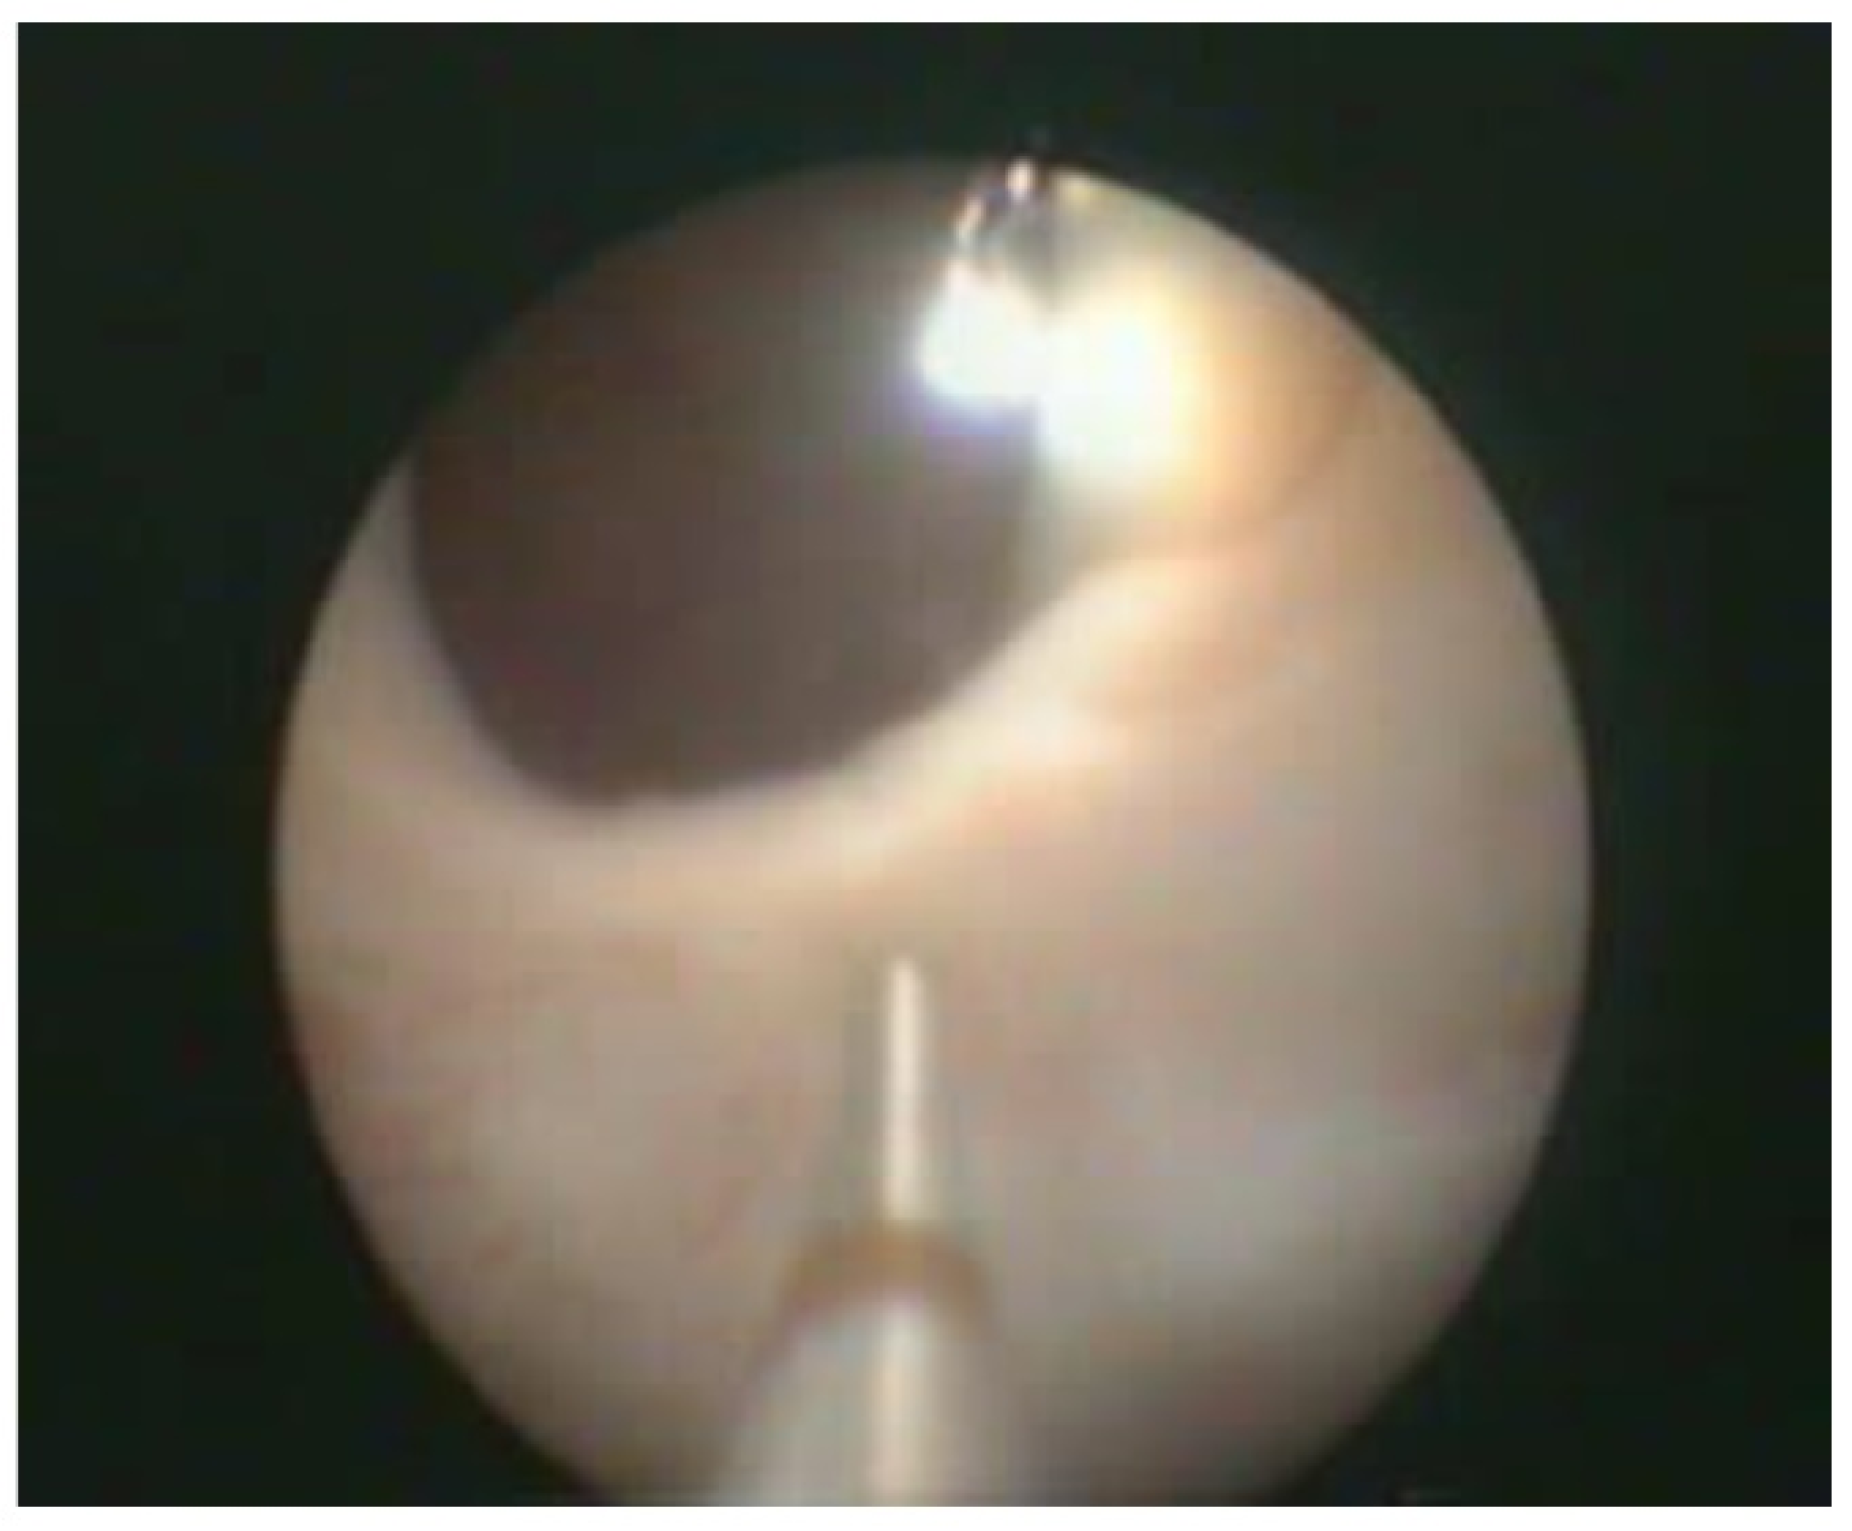

Figure 3.

Transurethral cystoscopy controlling the percutaneous suprapubic bladder access.